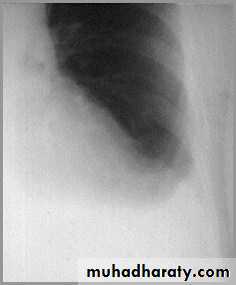

Differentiating the Causes of an Opacified Hemithorax

Atelectasis of an entire lungA large pleural effusion

Atelectasis of the Lung

There is a shift of heart and hemidiaphragm toward side of opacification (toward side of volume loss)Pleural Effusion